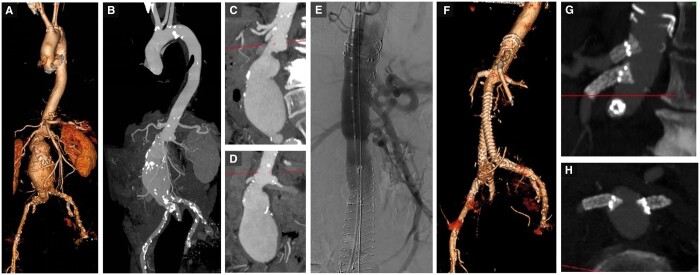

Endovascular aortic aneurysm repair (EVAR) is an established approach to treating abdominal aortic aneurysms, however, challenges arise when the aneurysm involves visceral branches with insufficient normal segment of the aorta to provide aneurysm seal without excluding those vessels. To overcome this, a range of technological developments and solutions have been proposed including fenestrated, branched, physician-modified stents, and chimney techniques. Understanding the currently available evidence for each option is essential to select the most suitable procedure for each patient. Overall, the evidence for fenestrated endovascular repair is the most comprehensive of these techniques and shows an early post-operative advantage over open surgical repair (OSR) but with a catch-up mortality in the mid-term period. In this review, we will describe these endovascular options, pre- and post-procedure radiological assessment and current evidence of outcomes.